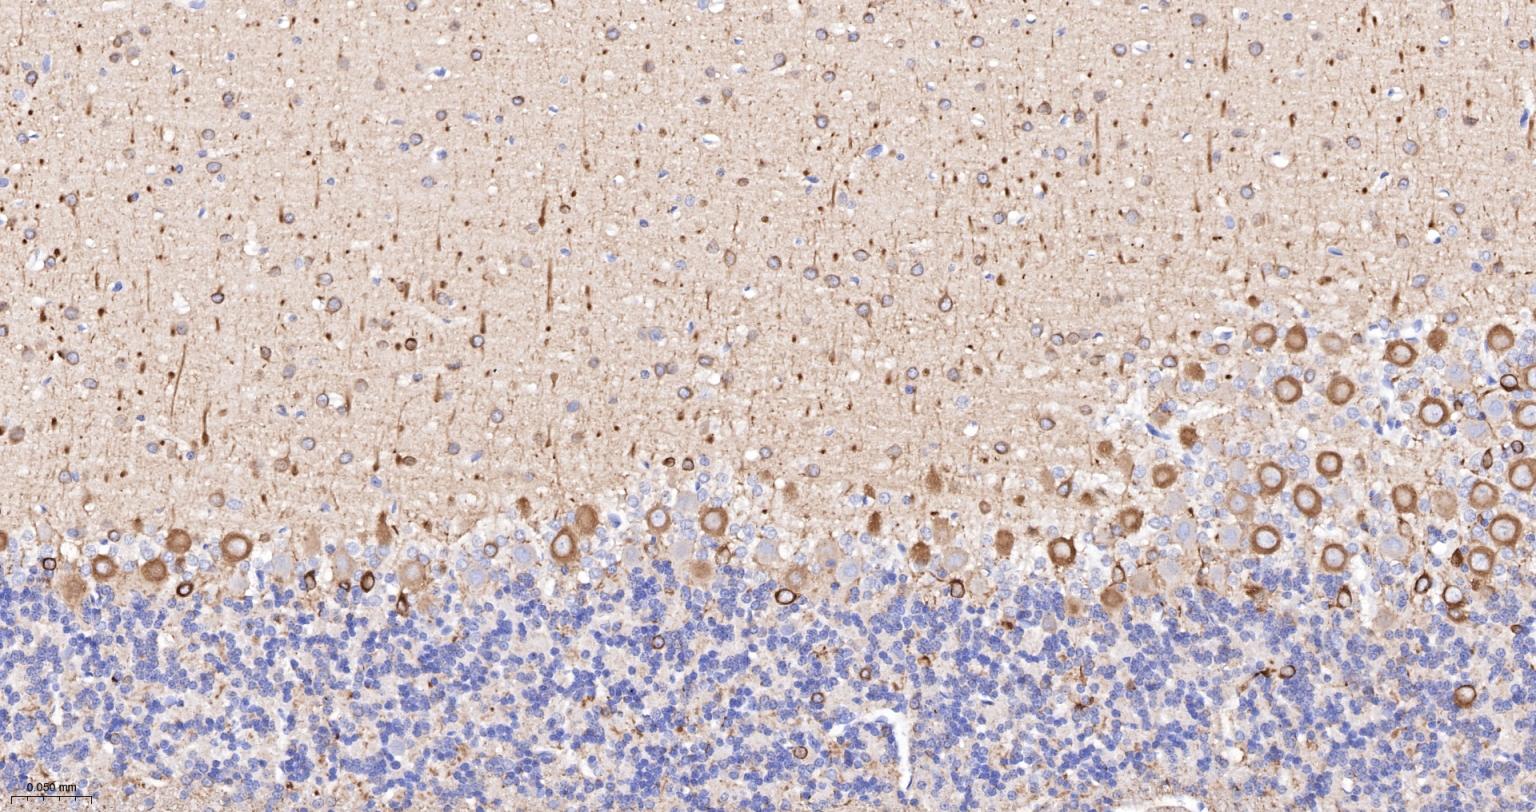

Paraformaldehyde-fixed, paraffin embedded (human cerebellum); Antigen retrieval by boiling in sodium citrate buffer (pH6.0) for 15min; Block endogenous peroxidase by 3% hydrogen peroxide for 20 minutes; Blocking buffer (normal goat serum) at 37°C for 30min; Incubation with (TUBB3 (Neuronal Marker) ) Monoclonal Antibody, Unconjugated (bsm-33177M) at 1:200 overnight at 4°C, followed by operating according to SP Kit(Mouse)(sp-0024) instructionsand DAB staining.

Paraformaldehyde-fixed, paraffin embedded (rat cerebellum); Antigen retrieval by boiling in sodium citrate buffer (pH6.0) for 15min; Block endogenous peroxidase by 3% hydrogen peroxide for 20 minutes; Blocking buffer (normal goat serum) at 37°C for 30min; Incubation with (TUBB3 (Neuronal Marker) ) Monoclonal Antibody, Unconjugated (bsm-33177M) at 1:200 overnight at 4°C, followed by operating according to SP Kit(Mouse)(sp-0024) instructionsand DAB staining.